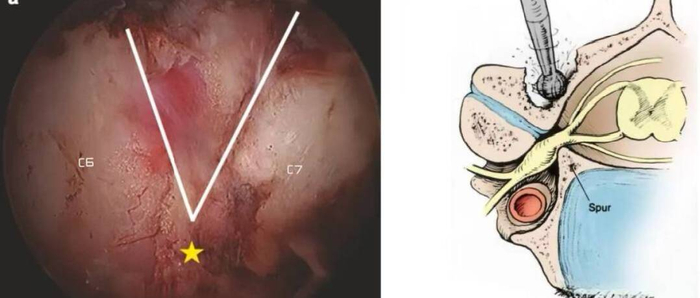

1.手术原理:经颈部后方两处0.5厘米微小切口,利用双通道内镜系统精准定位,切除突出椎间盘、扩大椎管容积,彻底解除神经根压迫。

2.术中优势:全程可视化操作避免损伤周围组织,出血量不足10ml,术后无需植入内固定物。

高红伟主任指出,相较于传统开放手术和单孔内镜技术,UBE-Keyhole具备三大核心优势:

1.超微创伤:切口仅如米粒大小,肌肉剥离少,最大限度保留颈椎结构;

2.安全高效:双通道设计扩大术野,可同时处理多节段病变,尤其适合复杂椎管狭窄病例;